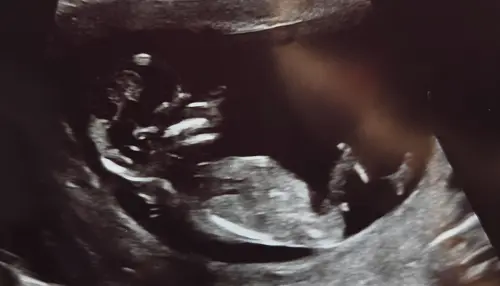

Vandaag 12+5. Ik heb vandaag de 13 weken echo gehad. Ik denk een meisje, wat denken jullie?

Wij afgelopen week ook de 13 weken echo gehad. Iemand enig idee ik zie het zelf helemaal niet namelijk 馃檭